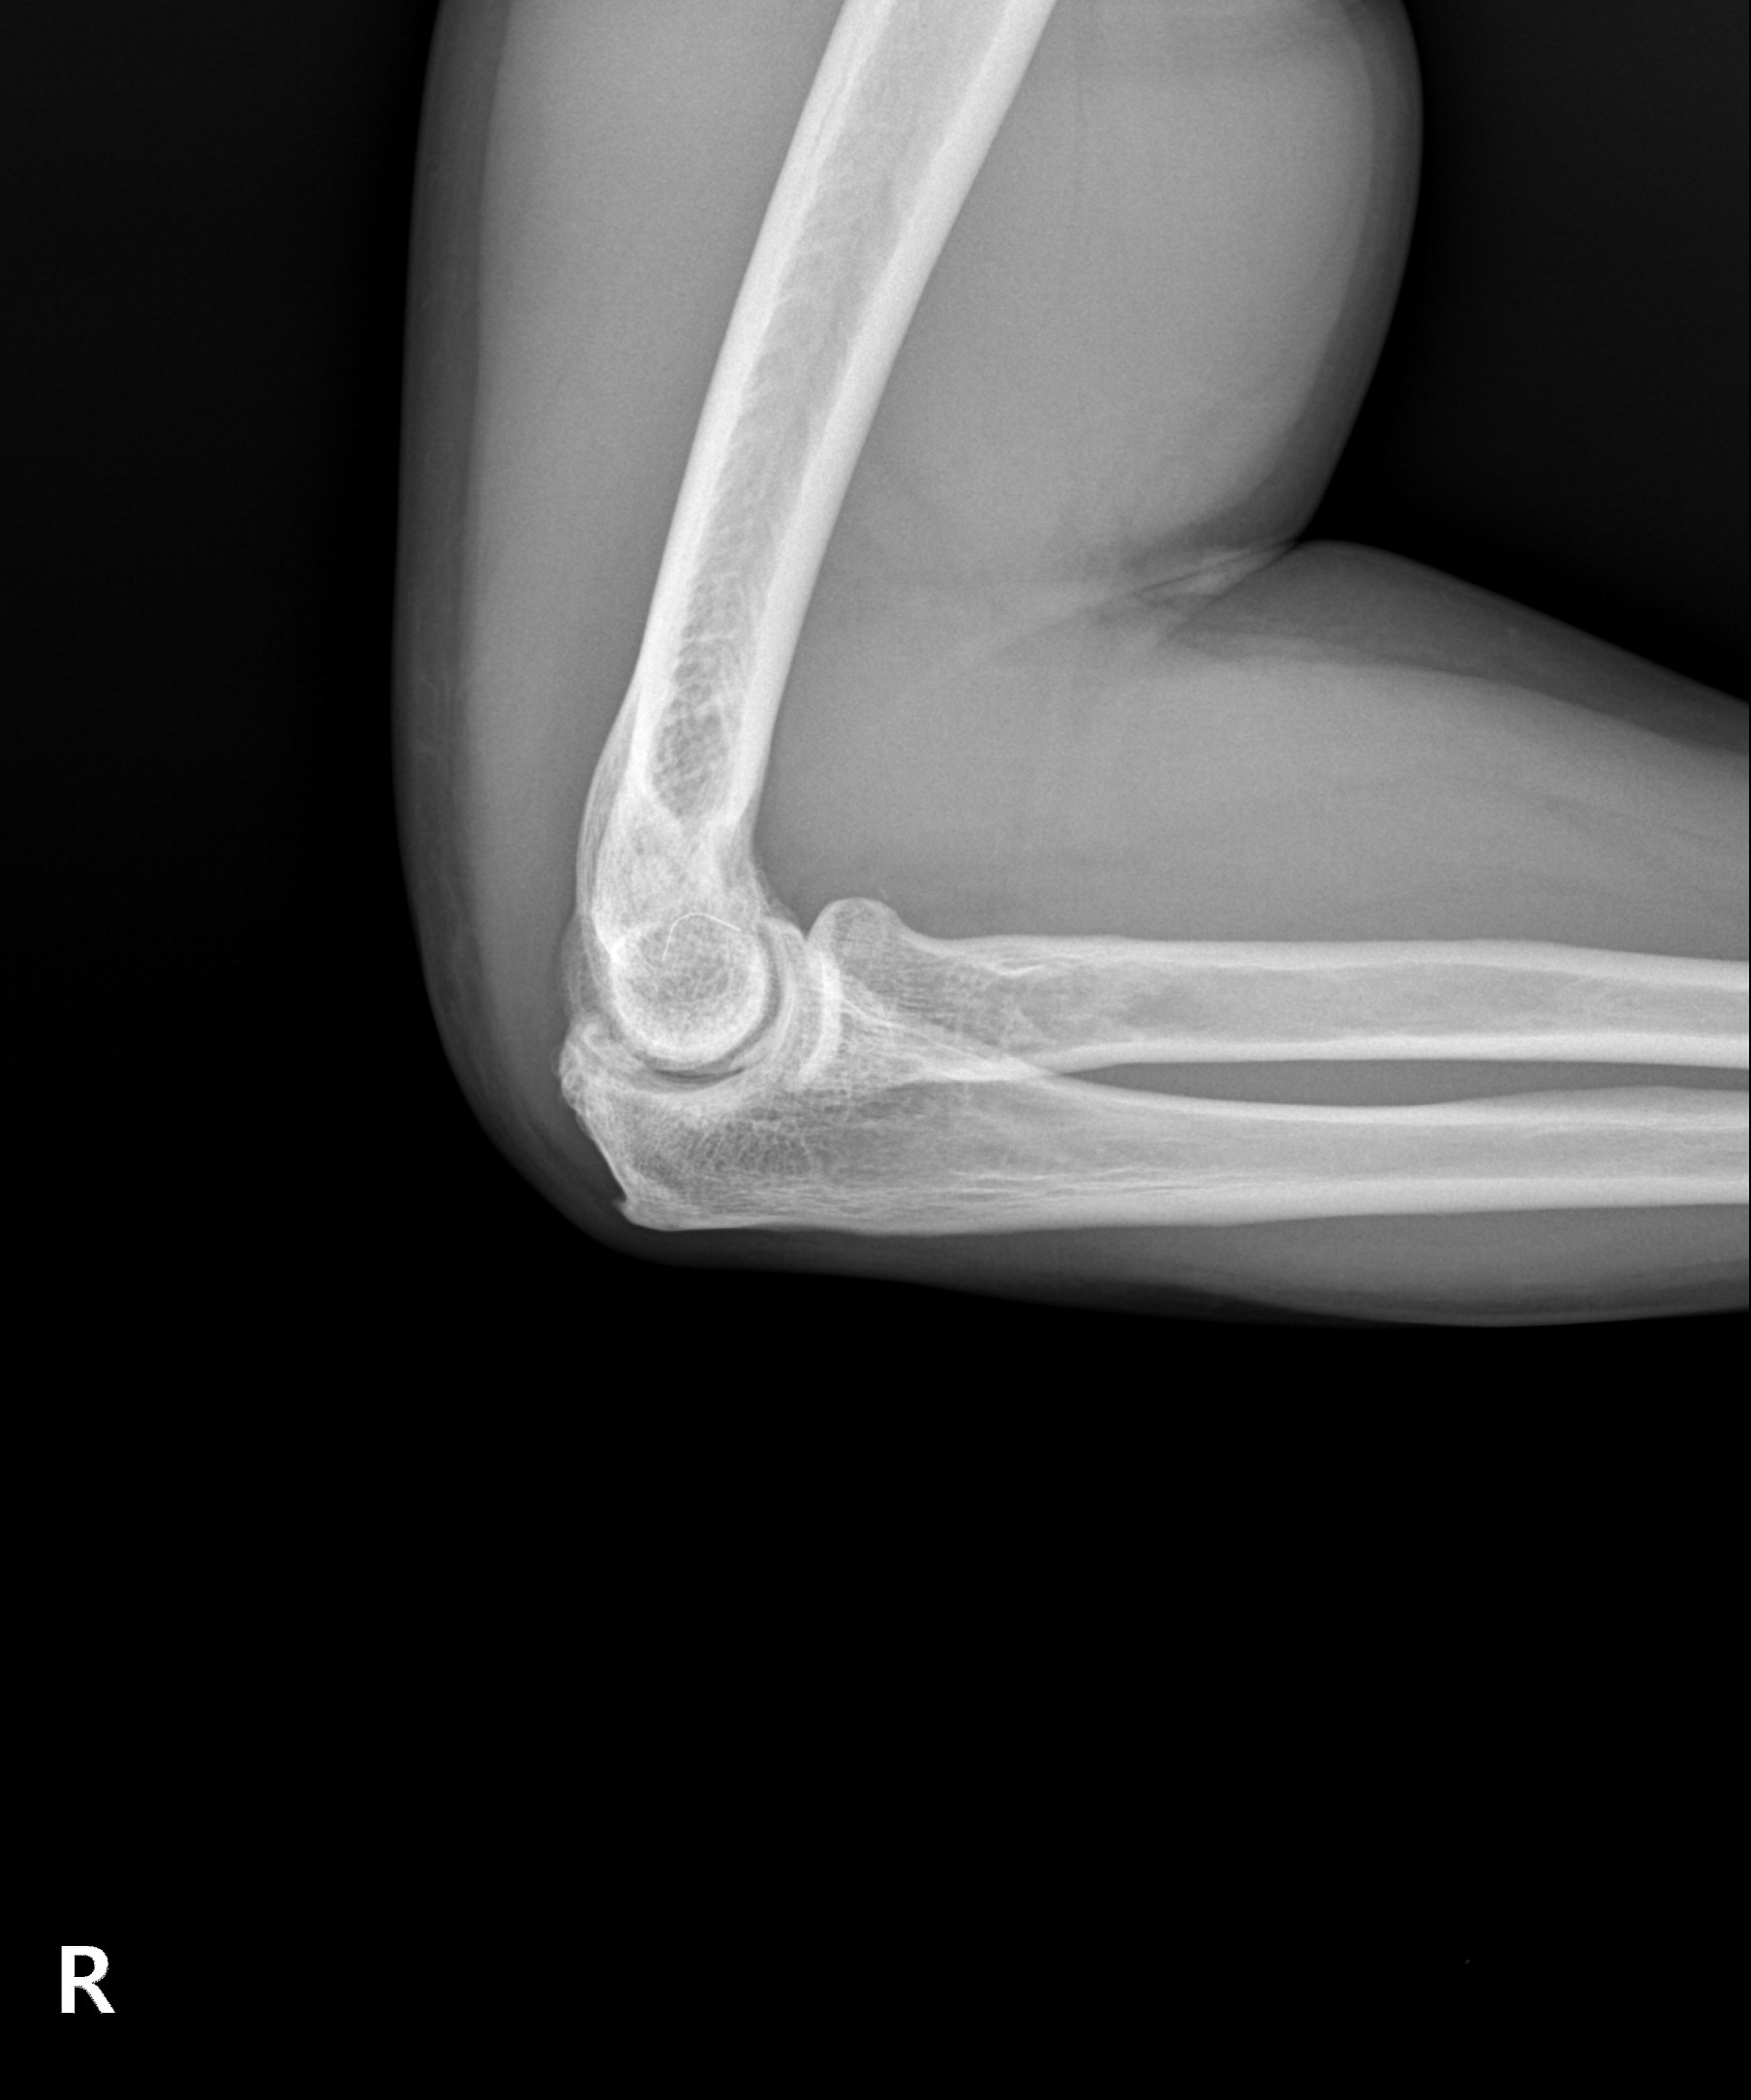

다른 부위 관절염처럼 팔꿈치 관절을 오랜 시간 과사용하여 관절이 손상되고 염증이 발생하는 질환입니다. 팔꿈치관절염은 시간이 지나며 점차 연골이 닳고 뼈가 자라나는 골극이 발생해 관절 가동 범위가 줄어들며 변형과 통증을 악화시킬 수 있습니다.

이미 관절 가동 범위에 제한이 온 팔꿈치 관절염은 뼈가 자라고

유리체 등이 관절면을 덮은 경우가 대부분으로 수술적 치료가 필요

팔꿈치 관절염 수술

관절내시경을 통해 자라난 뼈 조각과 관절 내 유리체를 제거하며

심한 경우 절개 수술이 함께 필요할 수 있습니다.